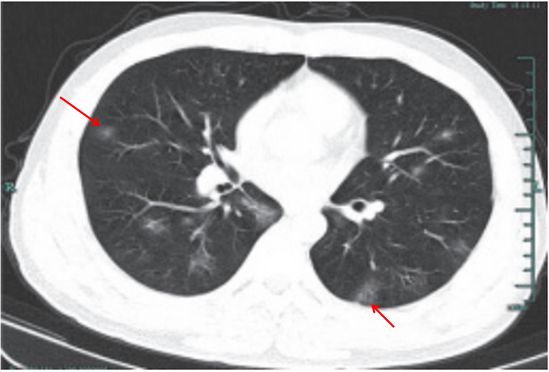

(1)呈单发或多发斑片 、 类 圆形 或结 节 影, 多位 于 胸膜下(图 3-11)。

(2)可出现小空洞、晕征,有时呈炎性肿块改变(图 3-12)。